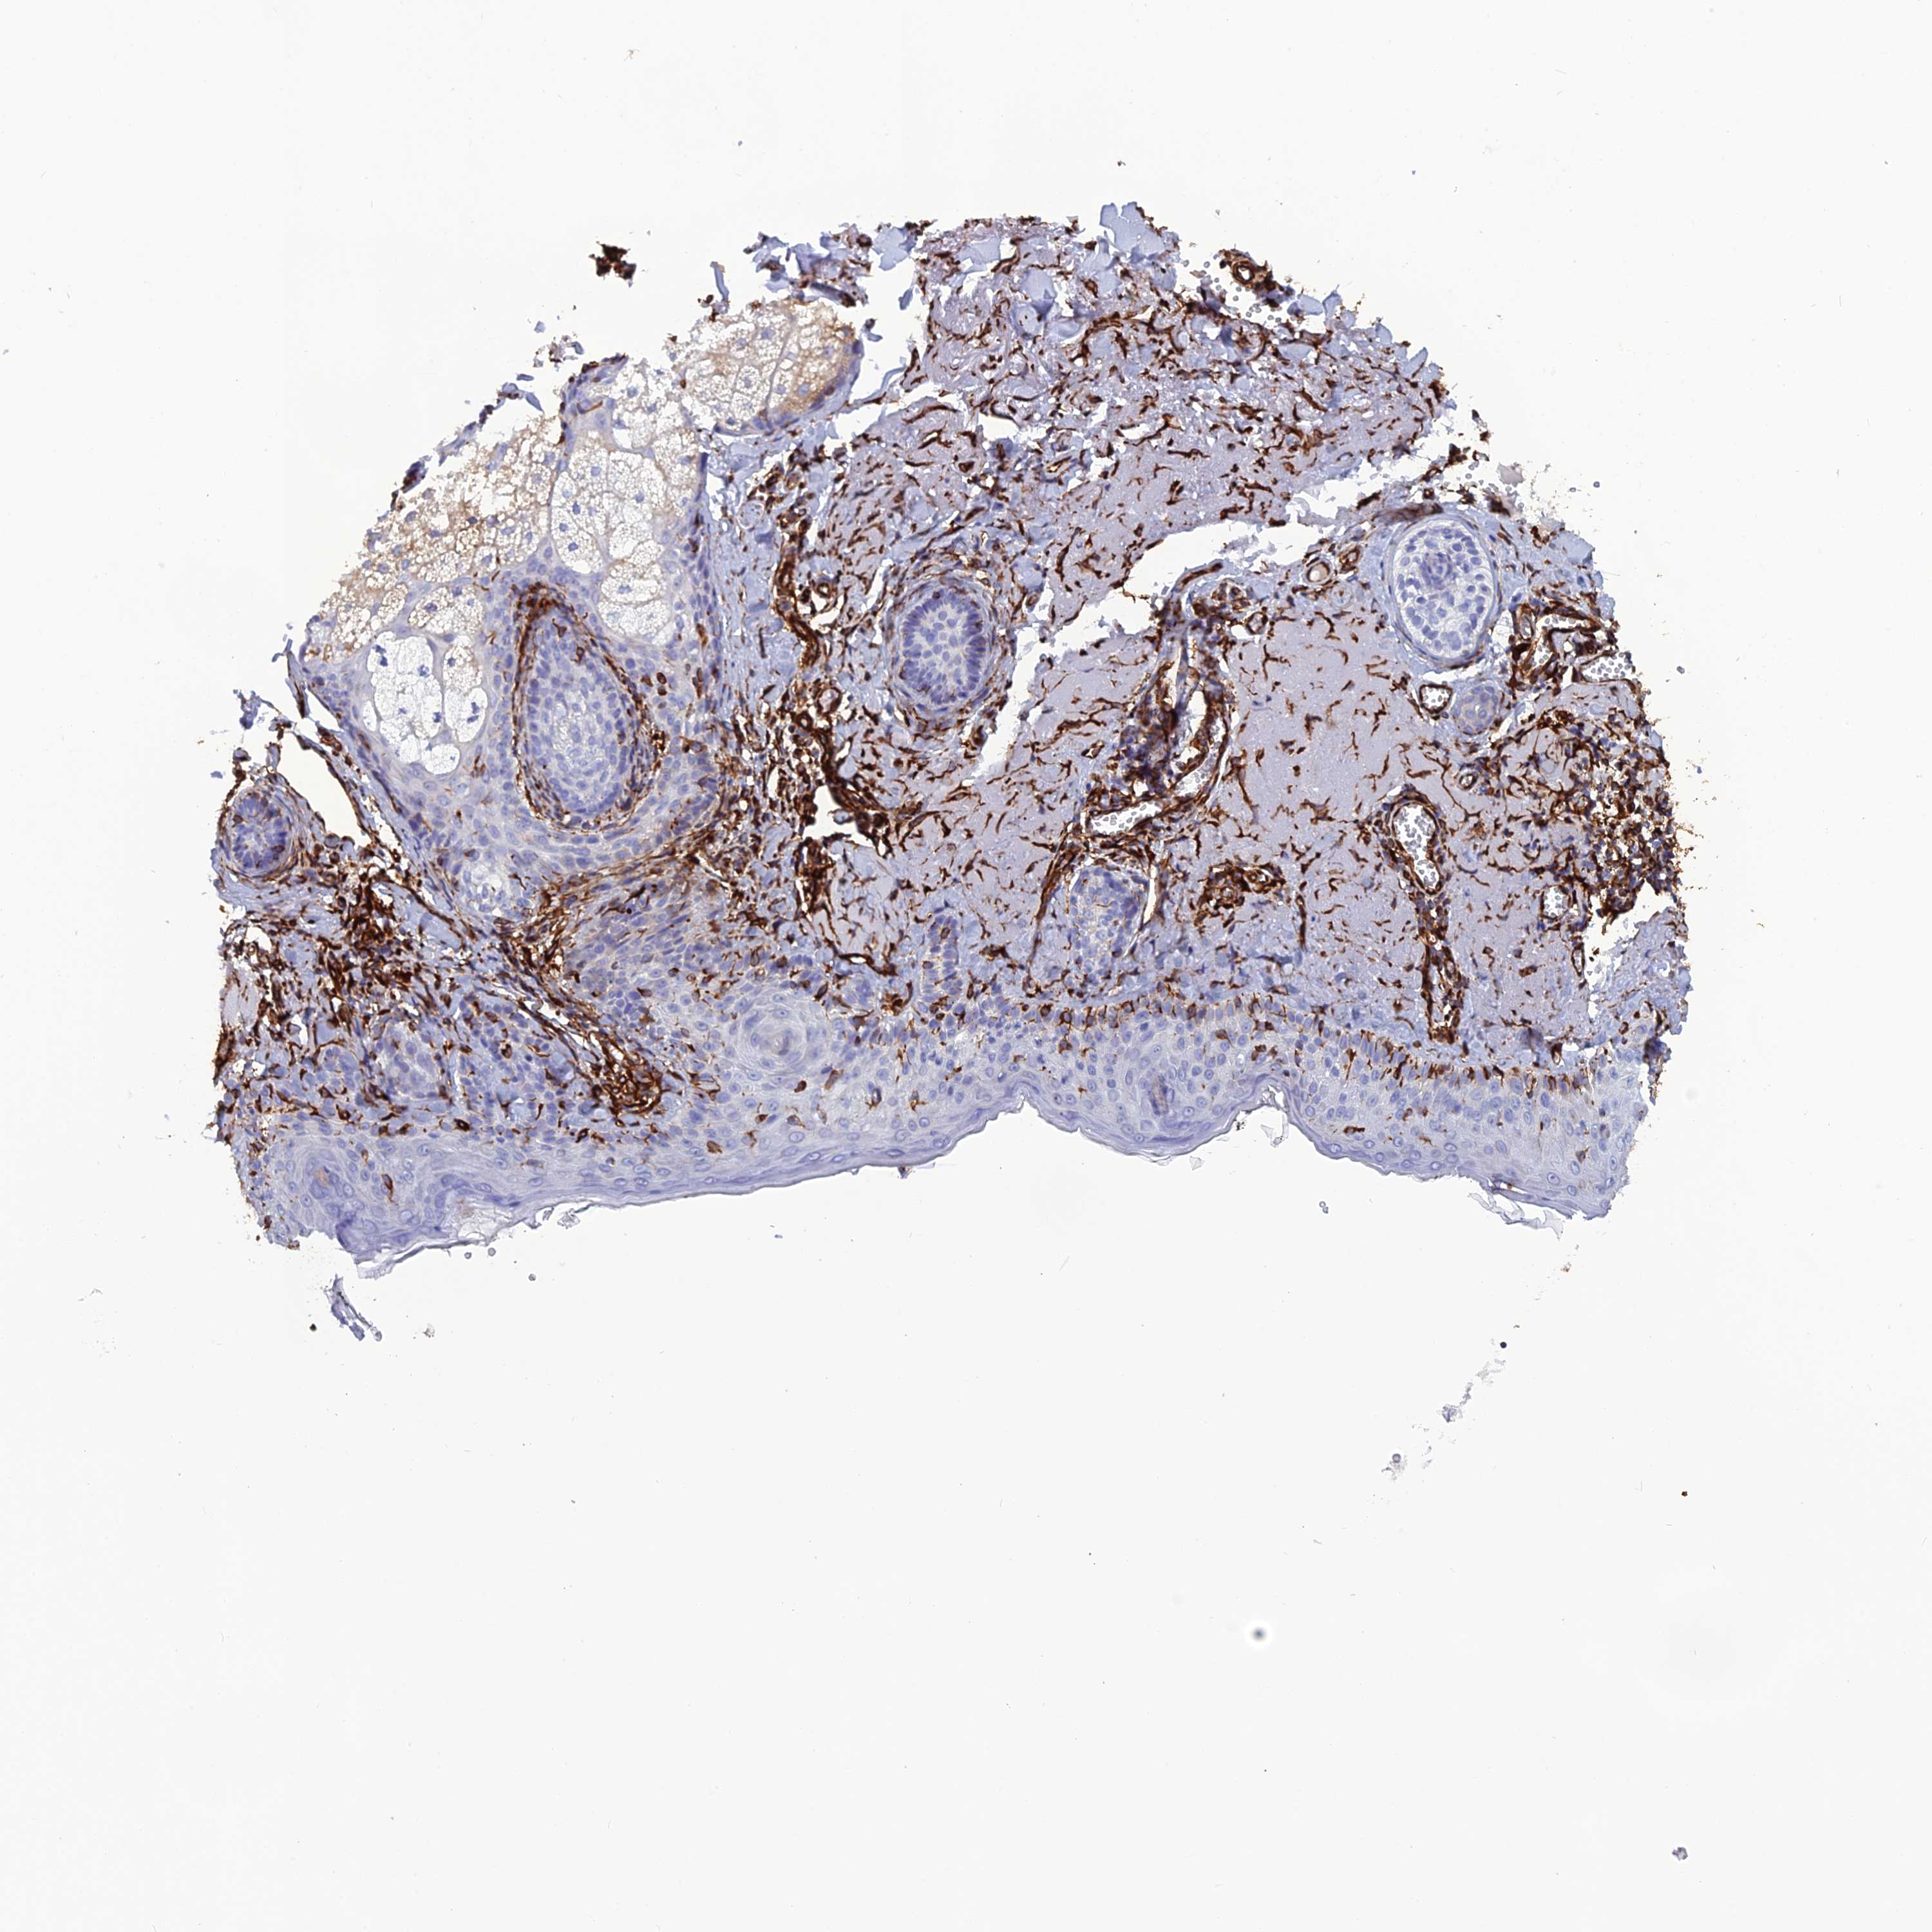

SKIN CANCER - Protein expressioni

A mouse-over function shows sample information and annotation data. Click on an image to view it in a full screen mode. Samples can be filtered based on level of antibody staining by selecting one or several of the following categories: high, medium, low and not detected. The assay and annotation is described here.

Antibody staining in the annotated cell types in the current human tissue is reported as not detected, low, medium, or high, based on conventional immunohistochemistry profiling in selected tissues. This score is based on the combination of the staining intensity and fraction of stained cells.

Each image is clickable and will lead to virtual microscopy that enables deeper exploration of all samples and also displays staining intensity scores, fraction scores and subcellular localization as well as patient and tissue information for each sample.

Antibody HPA050397

Staining

Intensity

Strong

Moderate

Weak

Negative

Quantity

>75%

75%-25%

<25%

None

Location

Nuclear

Cytoplasmic/membranous

Cytoplasmic/membranous,nuclear

Squamous cell carcinoma, NOS

Squamous cell carcinoma, metastatic, NOS